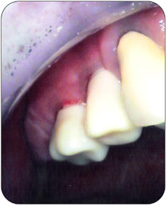

6 Monate später, Setzen der Zahnfleischformer

Einprobe der keramischen Stumpfaufbauten |